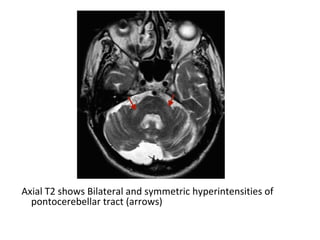

Axial T2 shows Bilateral and symmetric hyperintensities of

pontocerebellar tract (arrows)